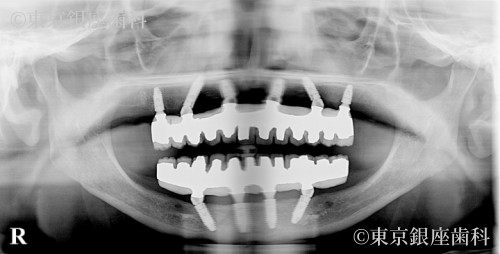

総入れ歯が合わず不便を感じていたが、上下ワンデイインプラントを選択。上顎には6本の埋入と骨補強を併用し、計画通りに進行。噛み合わせも改善し自然な見た目を取り戻した。

上下ワンデイインプラント(インプラント6本+骨補強)